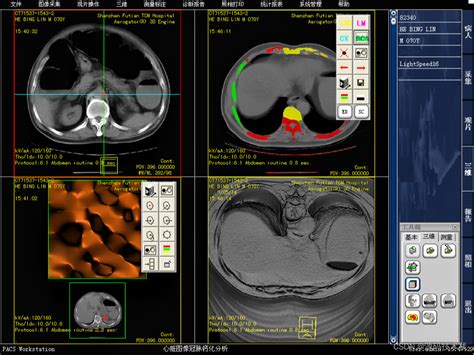

7、2 PACS系统的核心功能 影像采集通过医学影像设备如CTMRIX光机等采集影像数据 存储与传输数据数字化后存储在系统存储设备中,支持远程访问和传输,确保数据随时可用,并与其他医疗信息系统无缝对接 显示与诊断提供丰富的影像处理与诊断工具,辅助医生解读和分析影像数据3 PACS系统的优势。

8、PACS系统是影像归档和通信系统它是应用在医院影像科室的系统,主要的任务就是把日常产生的各种医学影像包括核磁,CT,超声,各种X光机,各种红外仪显微仪等设备产生的图像通过各种接口模拟,DICOM,网络以数字化的方式海量保存起来PACS系统的好处1减少物料成本引入PACS系统后,图像均采用。

13、2 该系统主要功能是存储和数字化医学影像资料,如核磁共振计算机断层扫描CT超声波等3 通过接口,PACS能够实现医学影像资料的传输和存储,授权用户可以快速检索影像4 此外,PACS提供辅助诊断管理功能,对影像资料的高效管理至关重要5 随着信息技术的快速发展,医学影像信息系统得到了计算机。

15、2 图像通讯与共享PACS系统实现了医疗机构内部各部门之间以及不同医疗机构之间的医学影像信息共享医生可以通过系统快速获取患者的影像资料,进行远程诊断和会诊,提高了医疗服务的效率和质量3 强大的后处理功能除了基本的存储和传输功能外,PACS系统还提供了图像的后处理功能,如图像的缩放增强。